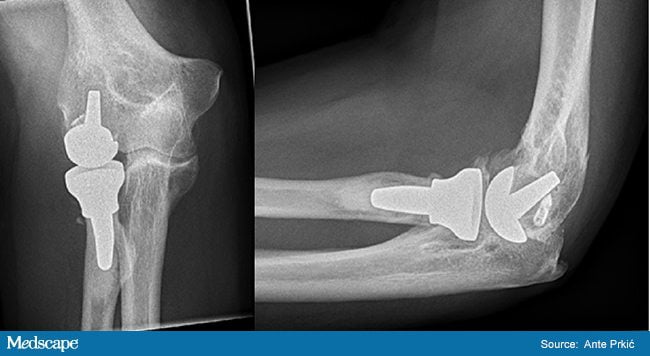

На 3 стадии заболевания больного беспокоит сильная боль, эффекта от лекарственных препаратов практически нет. При таких обстоятельствах поможет только хирургия. Применяется остеотомия – иссечение кости в месте поражения и фиксация ее в выгодном положении. При наличии остеофитов их удаляют.

В далеко зашедших случаях производится эндопротезирование локтевого сустава или головки лучевой кости. Оно показано при выраженной контрактуре или анкилозе (полное обездвиживание в локте). Пораженные костные участки иссекаются, на их место устанавливается протез. Его части крепятся к костной ткани оперируемого при помощи медицинского цемента.

После такого лечения больному предстоит период восстановления, который проводится в реабилитационных центрах или в домашних условиях под наблюдением врача.